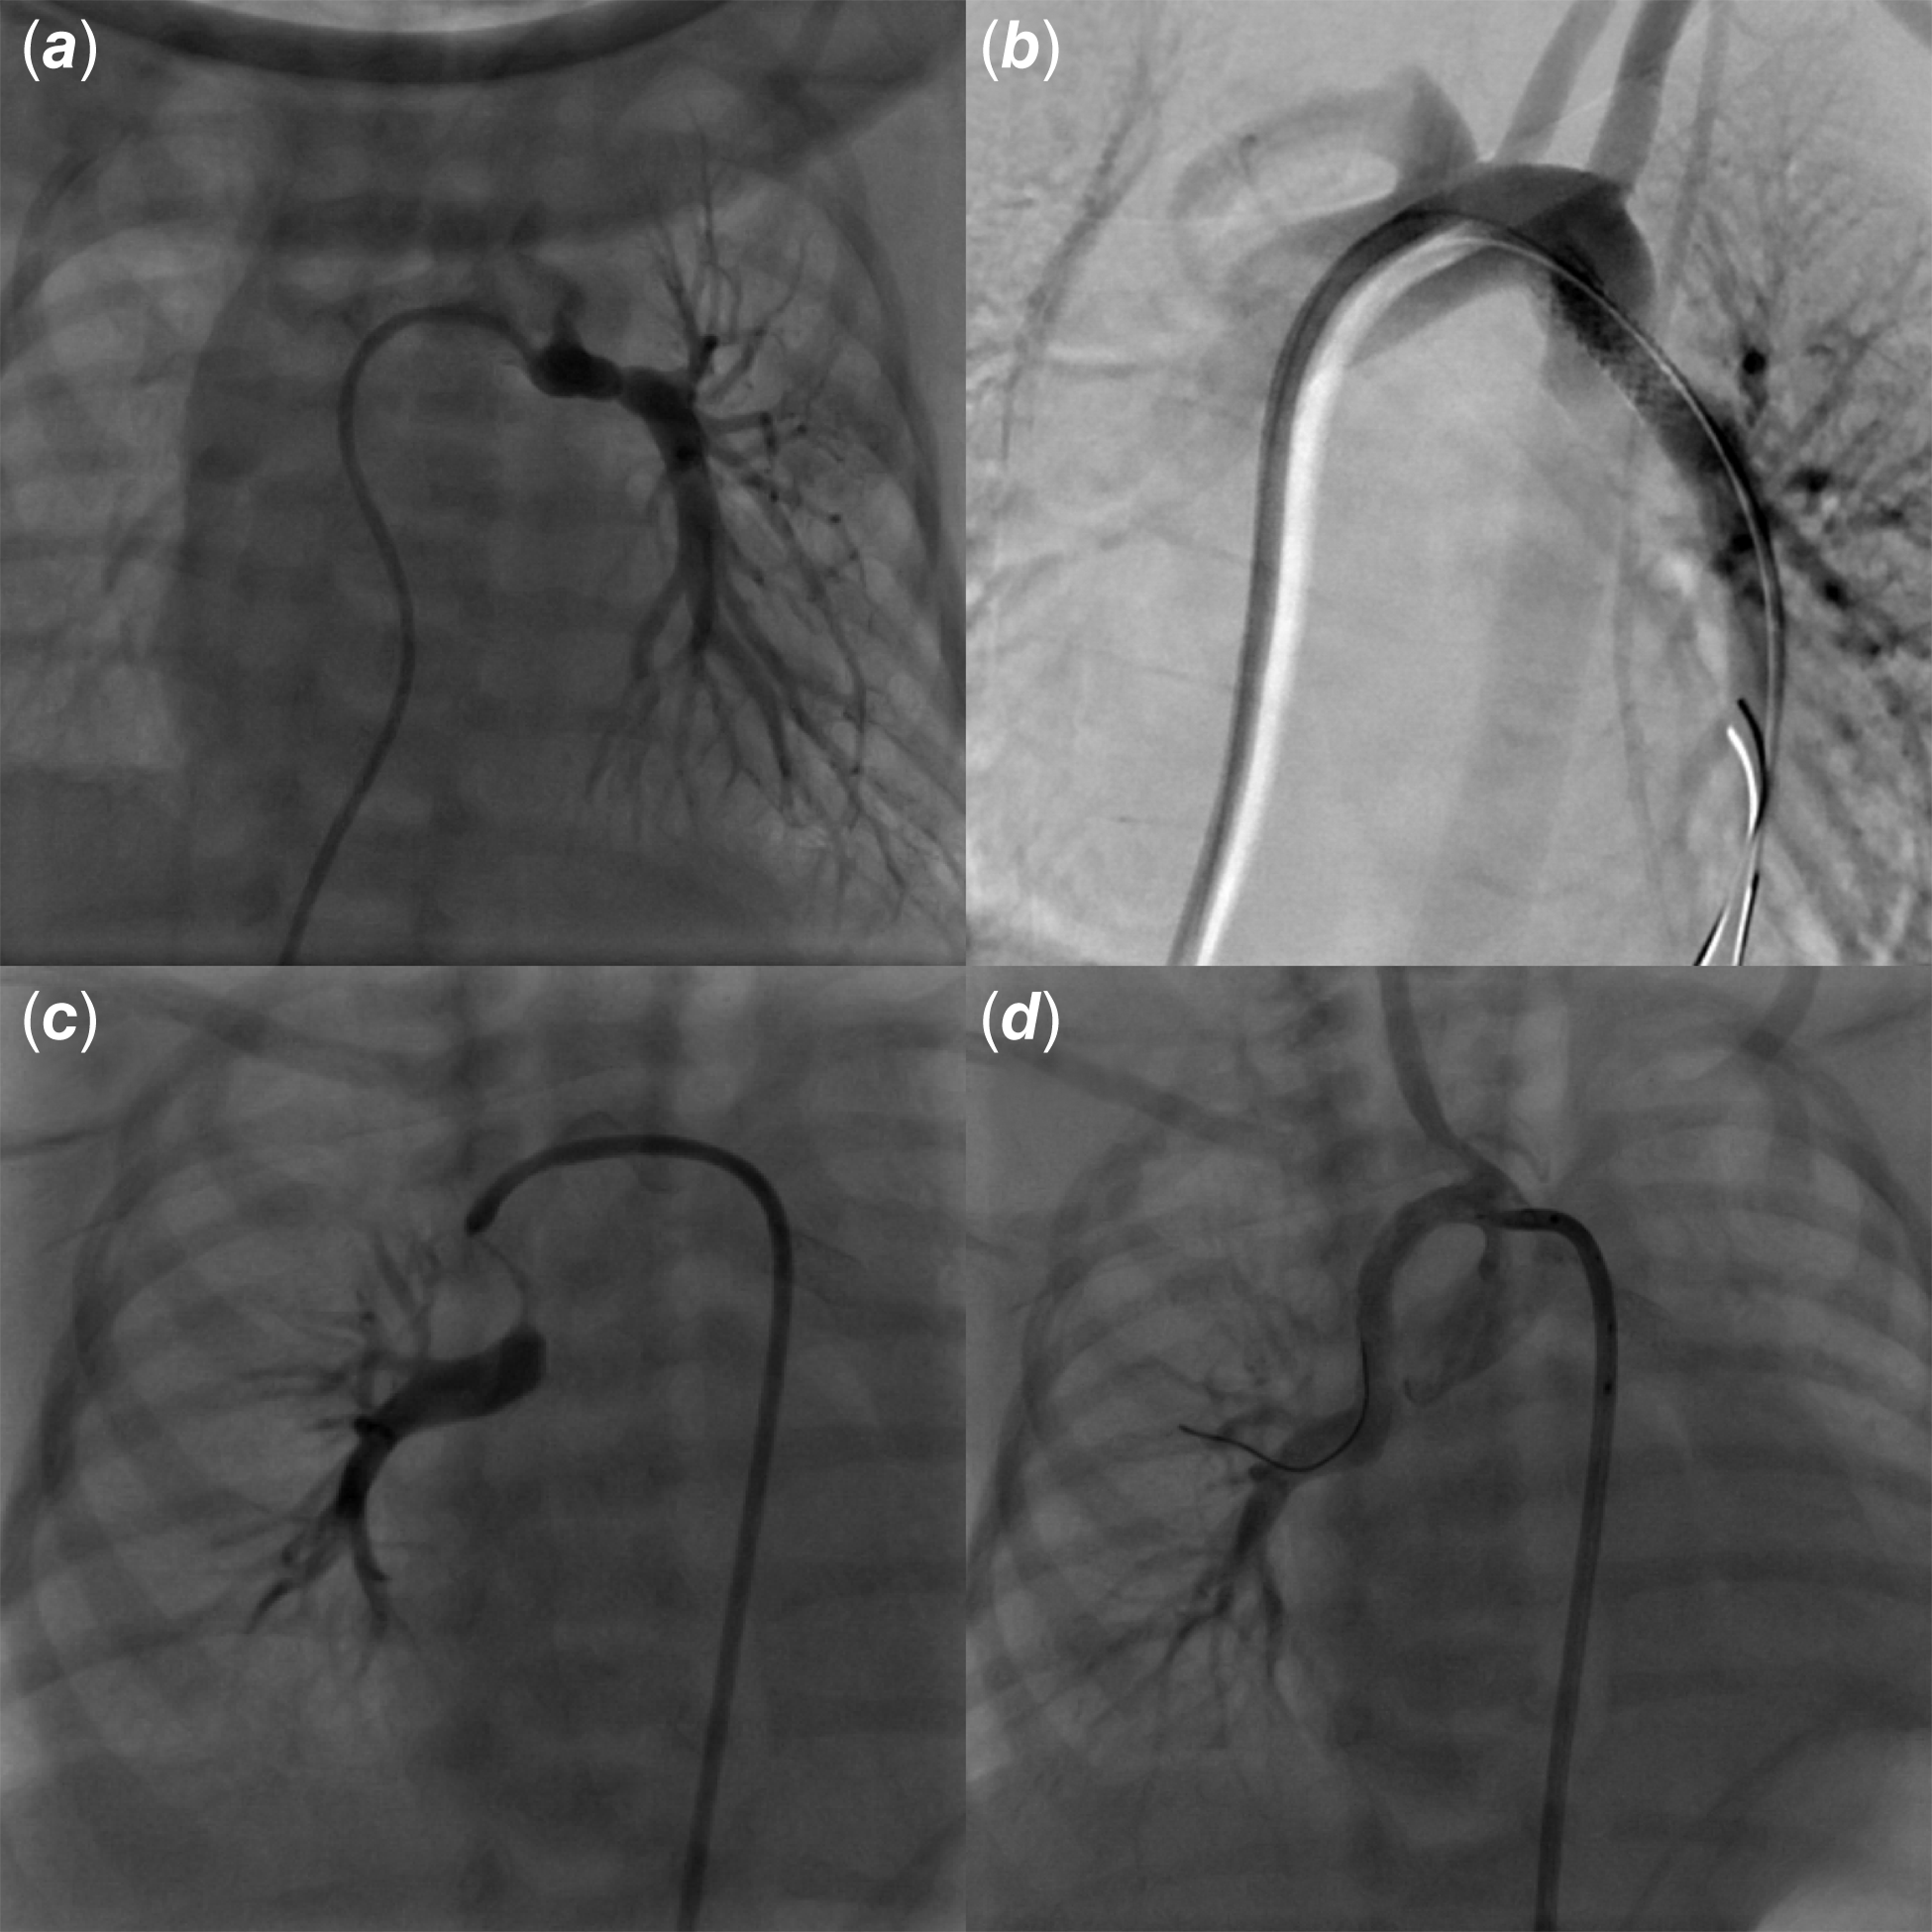

A 2500-gram term newborn was admitted in our department from the delivery room for the management of a prenatally diagnosed tetralogy of Fallot with pulmonary atresia. His peripheral oxygen saturation level was 80% on pulse oximetry in room air. Transthoracic echocardiography showed a normal atrial arrangement and confirmed a tetralogy of Fallot with pulmonary atresia and discontinuous pulmonary artery branches. At day-of-life 1, saturation dropped to 60%. Echocardiogram showed normally supplied right pulmonary artery but a constricted left ductus and functionally closed left pulmonary artery. Prostaglandin (PGE-1, 10 ng/kg/min) infusion was started and allowed restoration of the left pulmonary artery perfusion and subsequent improvement in oxygen saturation. A CT scan was performed to delineate ductal anatomy (Fig 1). After multidisciplinary team discussion, a transcatheter approach was preferred and the baby was transferred to the catheterisation laboratory. The left ventricular angiogram showed that the left pulmonary artery was supplied by a ductus arteriosus arising from the aortic arch, whilst the right pulmonary artery came straight from the brachiocephalic artery (Fig 1). There was no major aorto-pulmonary collateral artery. An elective ductal stenting with a 3.5 × 13 mm bare metal coronary stent was performed on the fifth postnatal day, with a 5-French Judkins Left 3.5 coronary guide catheter advanced through right ventricle into the aortic arch from the right femoral vein (Fig 2). PGE-1 had been stopped 6 hours before ductal stenting to allow the ductus to be well constricted. After ductal stenting, the baby was started on aspirin and clopidogrel. Four days later, oxygen saturation suddenly dropped again, up to 55%. Echocardiogram showed a well-positioned stent on the origin of the left pulmonary artery with an unrestrictive blood flow, but no right pulmonary artery was seen anymore. The patient was sent back to the catheterisation laboratory, where hand contrast injection demonstrated sub-occlusion of the proximal segment of the right pulmonary artery, which was consistent with ductal constriction of a second, right ductus arteriosus supplying the right pulmonary artery. Emergent ductal stenting of the right ductus was performed using a 3.5 × 24 mm bare metal coronary stent with a 5-French Judkins Right 3.0 coronary guide catheter into the brachiocephalic artery from the right femoral artery (Fig 2). This allowed clinical improvement and saturation increase up to 88%. Both stenting were uneventful, and the patient remained on aspirin and clopidogrel till surgical repair with pulmonary artery reimplantation 10 months later.

Figure 2. Bilateral arterial duct constriction and stenting. Hand injection via a 4-fr judkins right catheter engaged into the left ductus arteriosus delineating the left pulmonary artery ( a ). The left ductus was stented using a 3.5 × 13 bare metal coronary stent leading to successful recanalisation of the left pulmonary artery ( b ). Four days later, hand injection showing constricted right ductus arteriosus and functionally closed right pulmonary artery ( c ). The right ductus was stented using a 3.5 × 24 bare metal coronary stent leading to successful recanalisation of the right pulmonary artery ( d ).